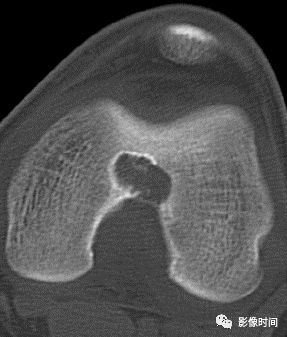

五、骨和软组织钙化

(一)瘤软骨钙化:瘤软骨常表现为环状钙化, 是诊断软骨类肿瘤较为可靠的影像学征象。环状钙化形成于环状软骨、以及软骨小叶边缘的软骨基质。钙质沉着可呈小点状、小条状、半环状或弧形;亦可浓密相连、重叠呈菜花状。钙化环的形态和密度可反映瘤组织分化程度, 通过观察钙化环的形态和密度,有助于良恶肿瘤的鉴别。

良性瘤软骨之瘤细胞分化好、生长缓慢、血供充分, 钙化环完整,密度高, 边缘清楚。良性软骨类肿瘤如骨软骨瘤(图 35)、软骨母细胞瘤(图 36)、内生软骨瘤(图 37)等均可于瘤组织内发生环形钙化。

恶性瘤软骨则呈密度淡薄, 边缘模糊的不规则钙化,恶性骨肿瘤的环形钙化,最多见于软骨肉瘤(图 38),其次是骨肉瘤。CT 是发现肿瘤内软骨钙化最为敏感的检查方法。

图 35  瘤软骨钙化:骨软骨瘤

图 36  瘤软骨钙化:软骨母细胞瘤

图 37  瘤软骨钙化:内生软骨瘤

图 38  瘤软骨钙化:软骨肉瘤